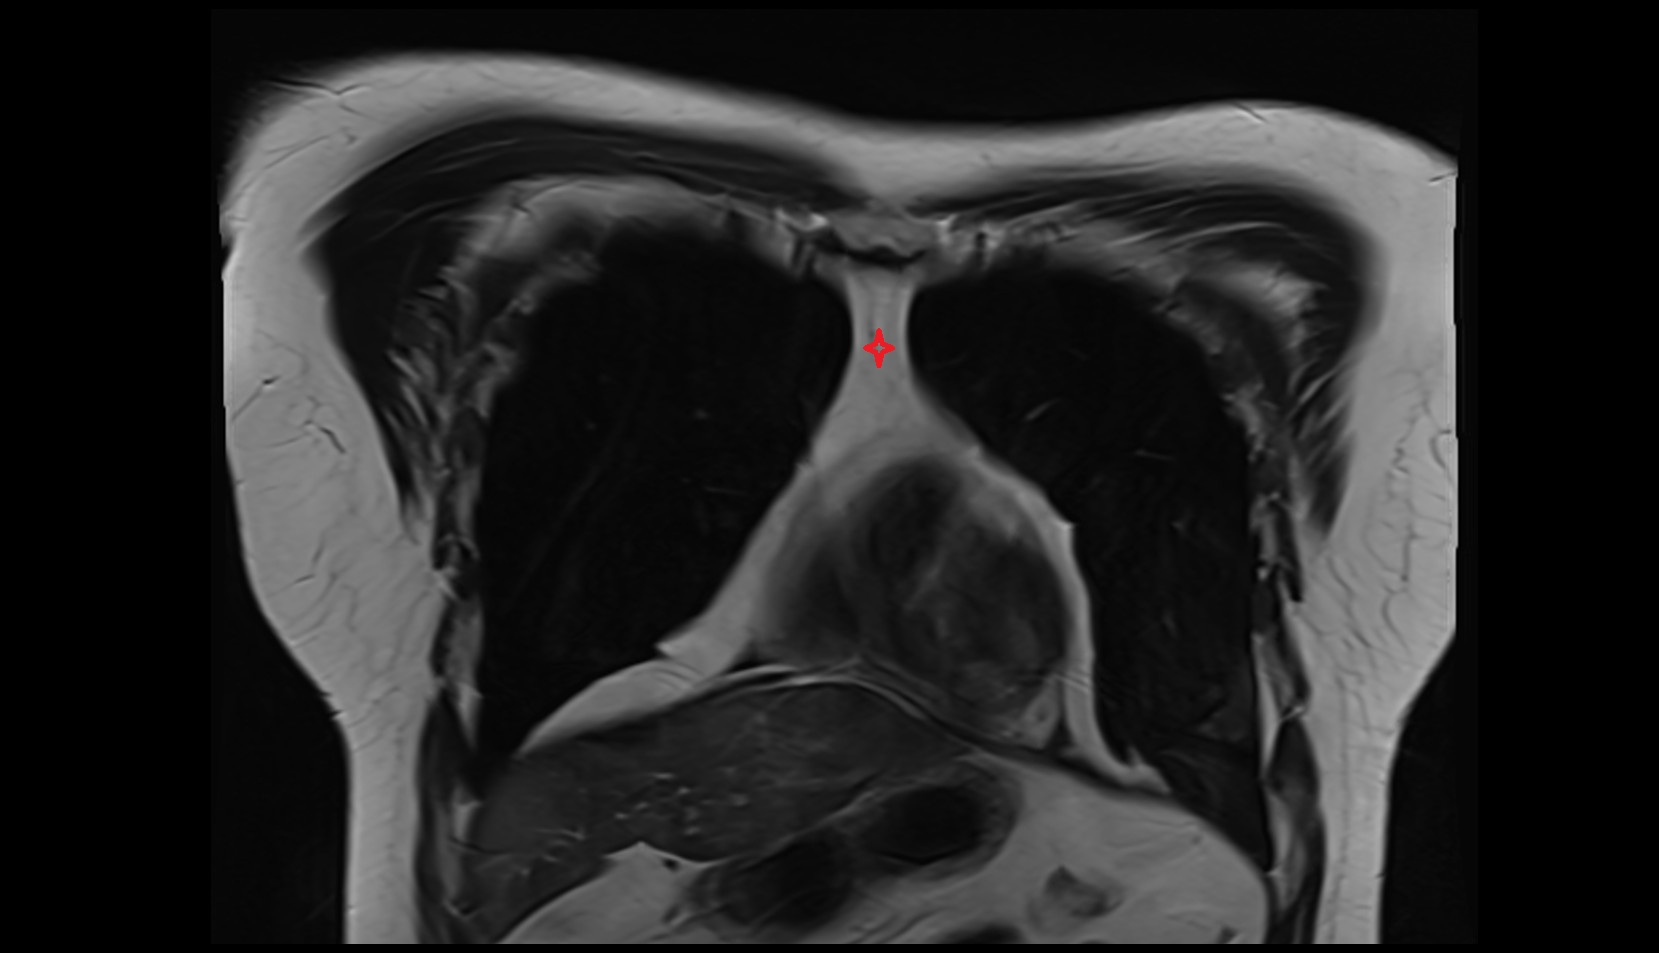

- Uterus

- Body of uterus

- Fundus of uterus

- Cervix of uterus

- Isthmus of uterus

- Endometrium of uterus

- Myometrium of uterus

- Perimetrium of uterus

- Junctional zone of uterus